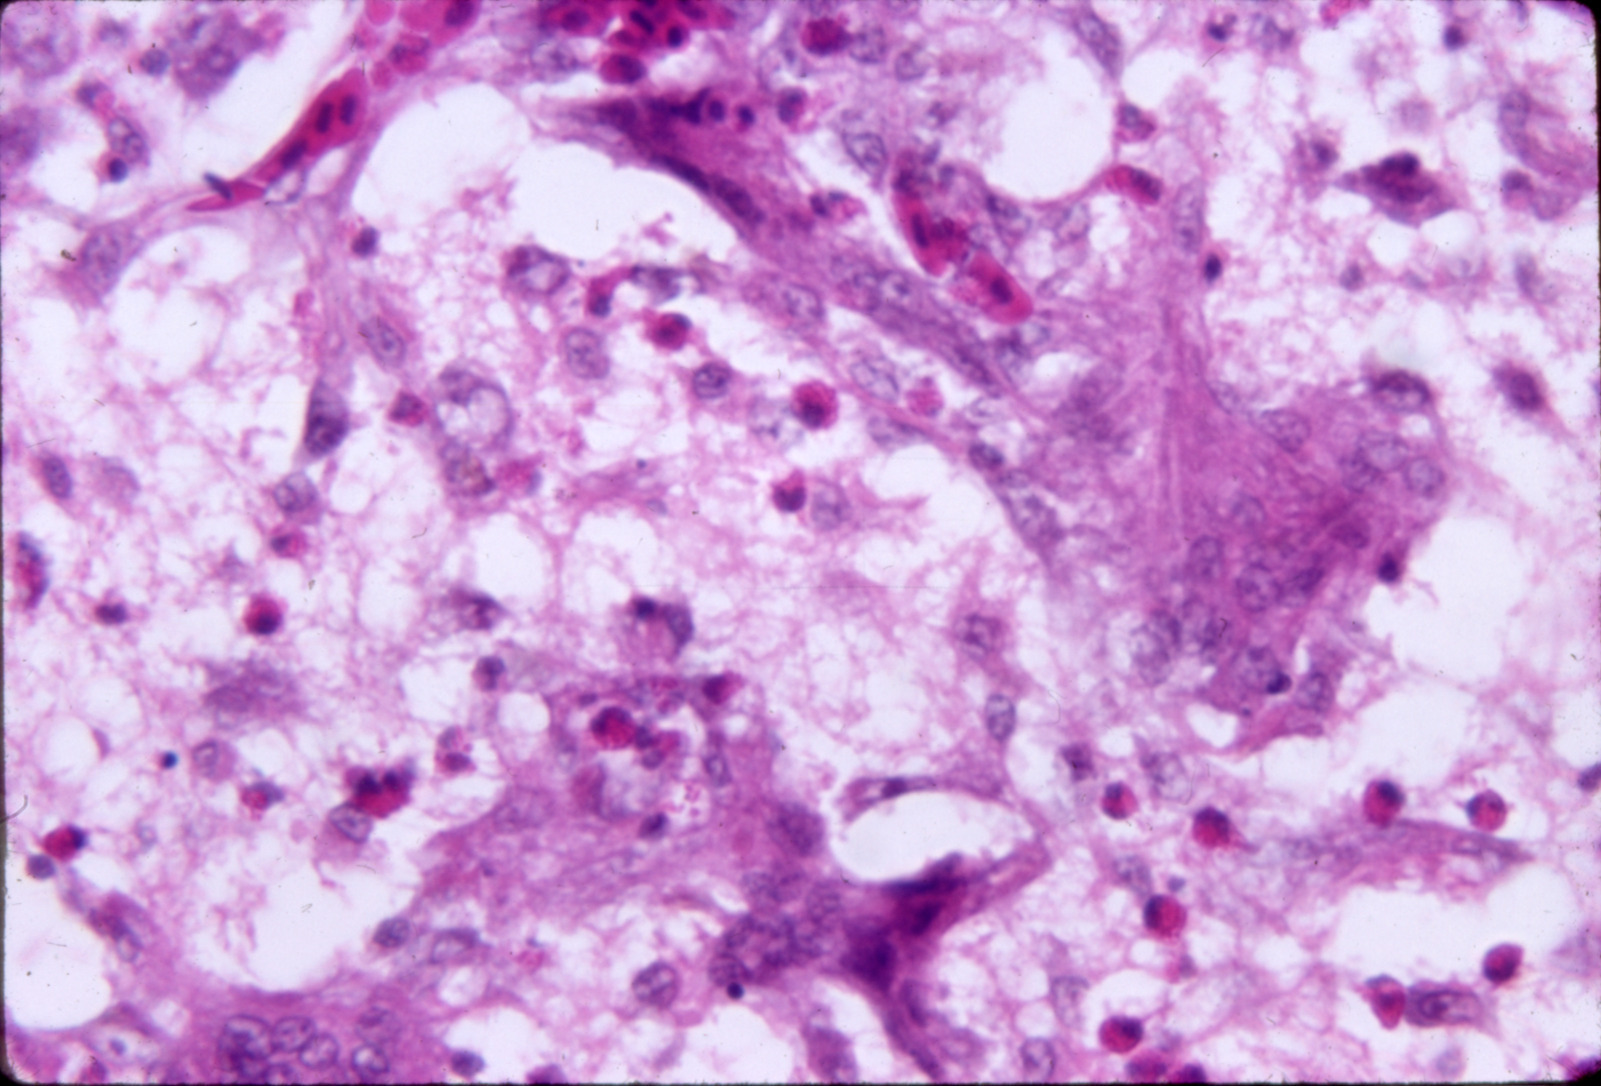

Aspergillosis-dactylariosis (slide study set no. 9)

Poultry--Diseases Aspergillosis

Slide Study Set #9, Aspergillosis-Dactylariosis (includes 24 color slides), 1978